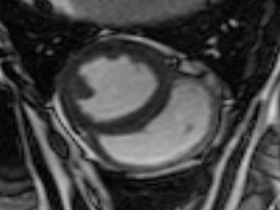

Easy-Trigger ist ein Medizinprodukt für die Herz- und Gefäßbildgebung in der Magnetresonanztomographie (MRT), das bifunktional bei Ungeborenen und Erwachsenen eingesetzt werden kann. Als weltweit erstes und einziges MRT-taugliches Doppler-Ultraschallgerät ermöglicht es erstmals Kombinationsuntersuchungen von MRT und Ultraschall. Der Ultraschallkopf wird auf dem Bauch oder über dem Herzen des Patienten platziert. Es ermöglicht erstmals die zeitliche Abstimmung der Herzaktion von ungeborenen Kindern mit dem MRT und damit MRT-Untersuchungen des kindlichen Herzens. Des Weiteren kann es zur Überwachung der Ungeborenen bei MRT-Untersuchungen von Schwangeren eingesetzt werden. Durch die Verwendung der Doppler-Ultraschall-Technik ist die Anwendung am Erwachsenen im Vergleich zum EKG robuster, einfacher und sogar bei höheren Feldstärken einsetzbar, bei denen das EKG nicht mehr zuverlässig arbeitet.

Cardiac MRI of the Fetal Heart Using a Novel Triggering Method: Initial Results in an Animal Model.

J Magn Reson Imaging. 2012 May;35(5):1071-6.